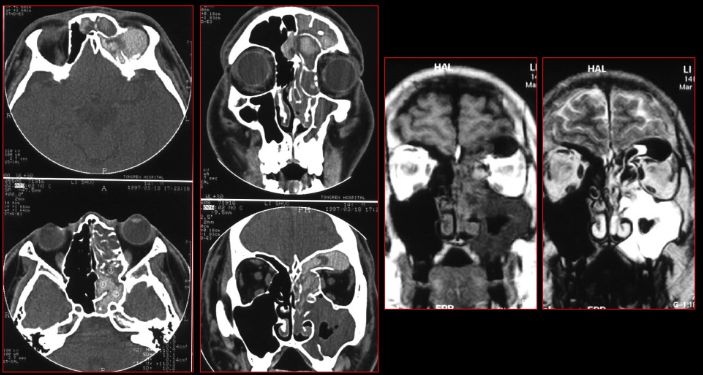

蝶窦炎—眶尖综合症

鼻窦炎—眶尖综合症

鼻窦炎—骨质增生及脑膜炎